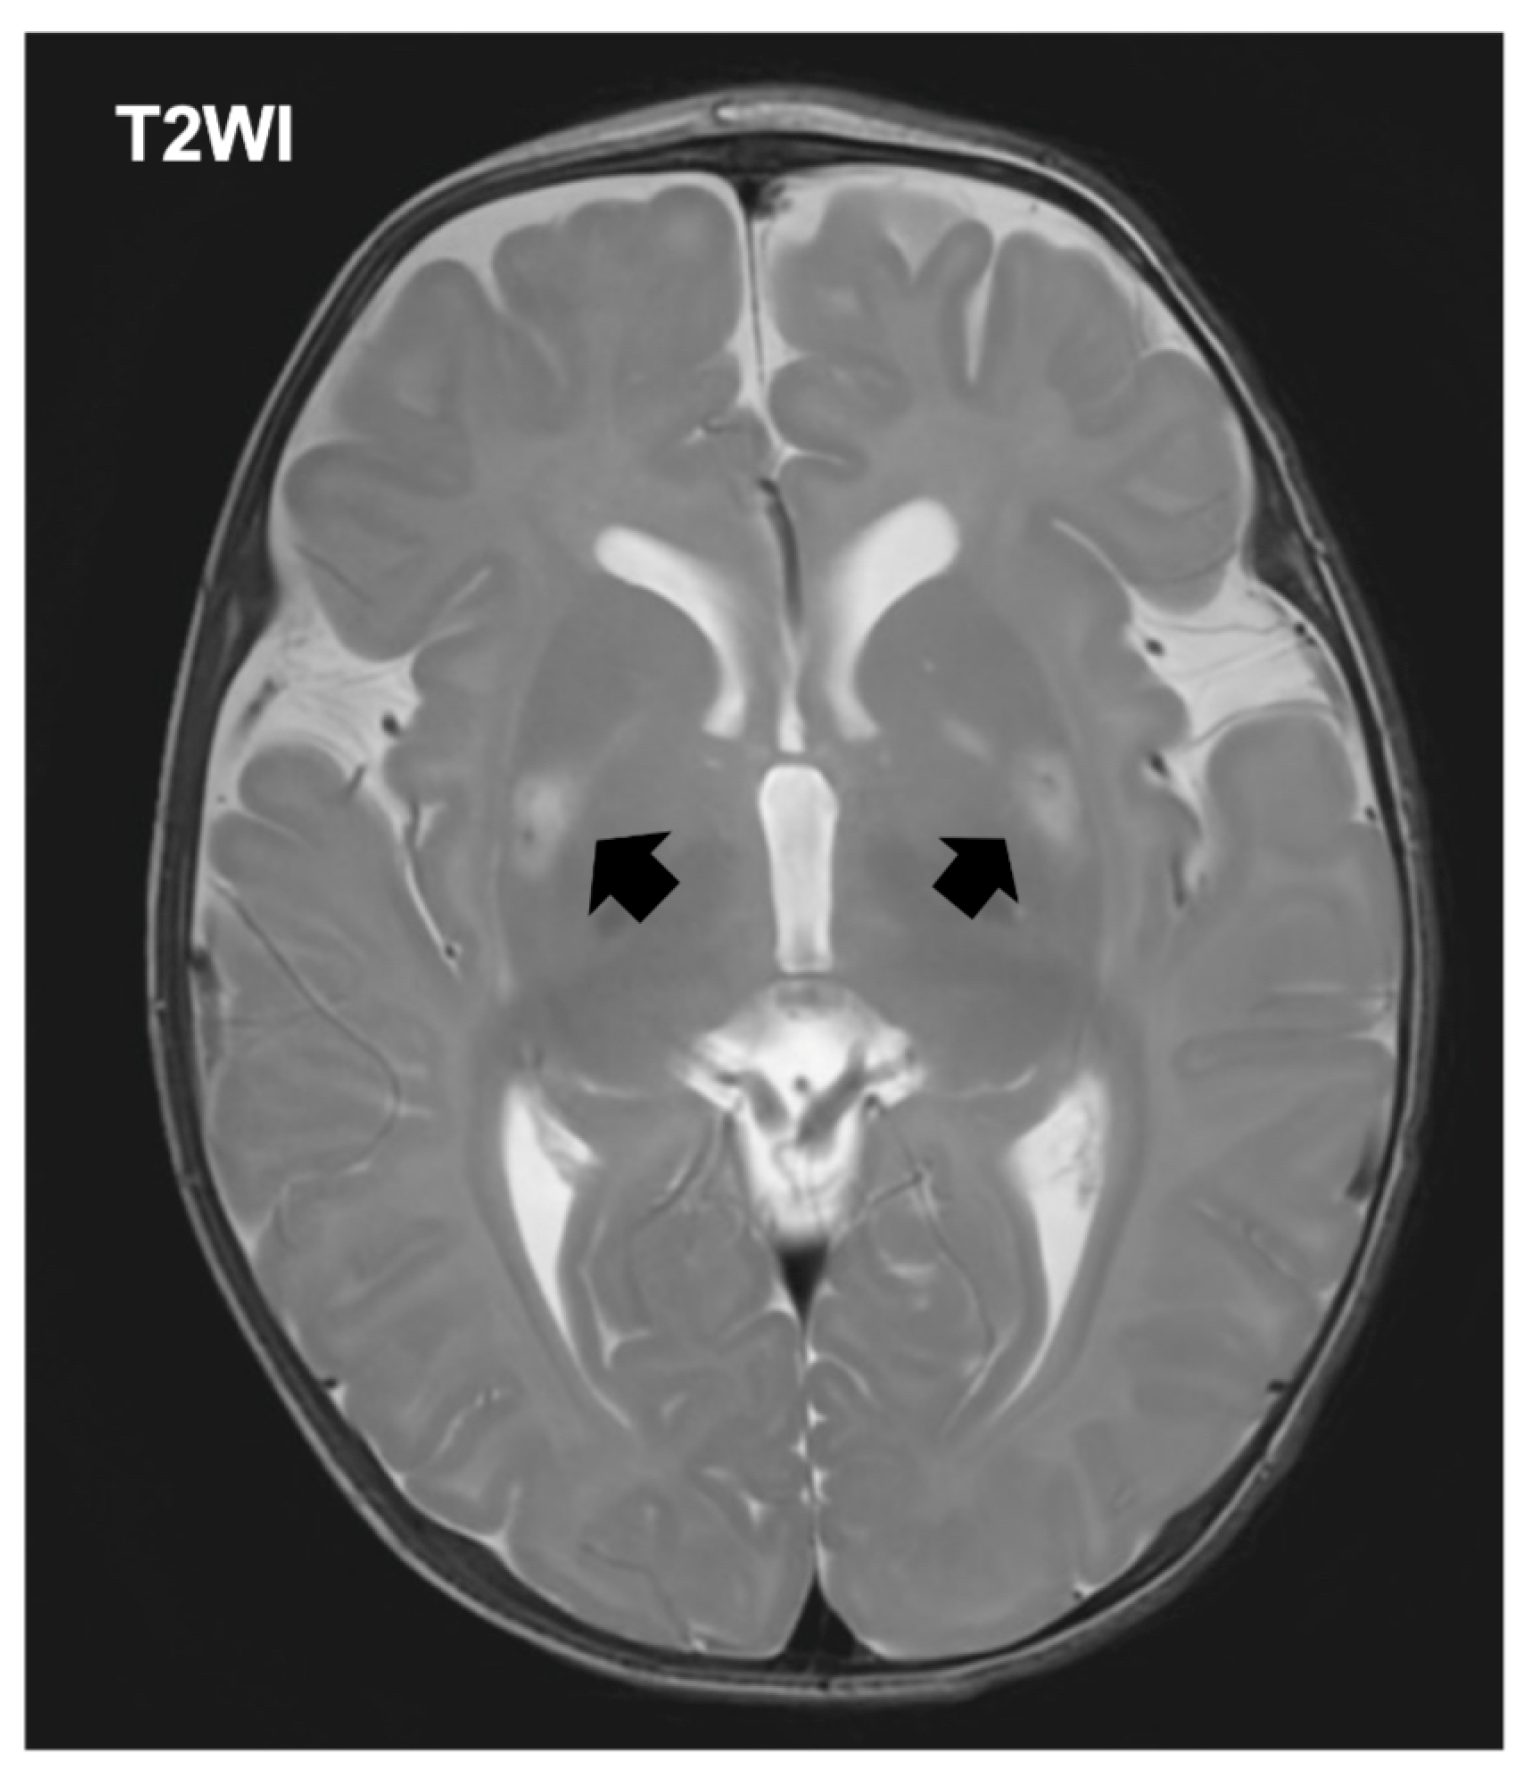

The patient was referred to a tertiary pediatric hospital for specialized evaluation including neuroimaging and genetic testing. The initial laboratory evaluation demonstrated hyperlactatemia with a plasma lactate level of 4.0 mmol/L (normal range [NR]: 0.5–1.6), accompanied by an elevated pyruvate concentration of 2.63 mmol/L (NR: 0.03–0.10). Creatine kinase was within reference limits at 63 U/L (NR: 34–204). Notably, ammonia was below the institutional reference interval at <9 μmol/L (NR: 11–51). Brain MRI revealed symmetric signal abnormalities in the basal ganglia bilaterally, consistent with the characteristic pattern observed in Leigh syndrome (Figure 1). Expanded exome sequencing using a hybrid nuclear exome and mitochondrial DNA panel identified a pathogenic variant in the MT-ATP6 gene (m.8993T>G), confirming the diagnosis of MT-ATP6-related mitochondrial disease manifesting as Leigh syndrome (OMIM:551500). The mutation load in blood was determined to be greater than 90%, consistent with the severe phenotype observed (Table S1).

Figure 1. Axial T2-weighted brain MRI at 4 months of age demonstrating bilateral basal ganglia hyperintensities (arrows).